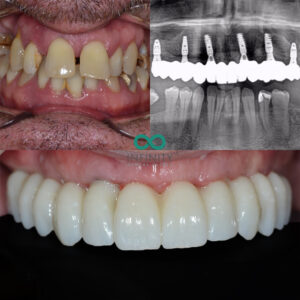

This patient attended our clinic wanting to pursue treatment to replace his failing and missing upper teeth. He was aware of the deteriorating problem over many years however, he was ‘hanging’ onto his teeth due to the fear of being without teeth. The fear of having to spend any time without teeth whilst undergoing treatment to replace teeth is somthing that often puts patient’s off undergoing the treatment they so dearly need.

After a thorough assessment we planned a treatment process whereby this patient would never be without fixed teeth. Our CBCT assessment and 3-Dimensional simultations enabled us to predictably design and manufacture replacement teeth that would fit ‘perfectly’ into his mouth and conform to his ‘style’.

On the same day that he had his teeth removed, we placed bone grafts, gum grafts, dental implants and fitted the replacement teeth. All in the same day!

Following this day of treatment he already had a life changing smile. Over the following 6 months his bone and gum grafts continued to heal and then we simply replaced his ‘initial’ teeth with his ‘final’ teeth. the final teeth are a further improvement to his initial teeth, designed to be even more customised to ensure they stand the test of time.

This patient was able to undergo treatment that he so dearly needed without ever having to be without any of his teeth – truly life changing!